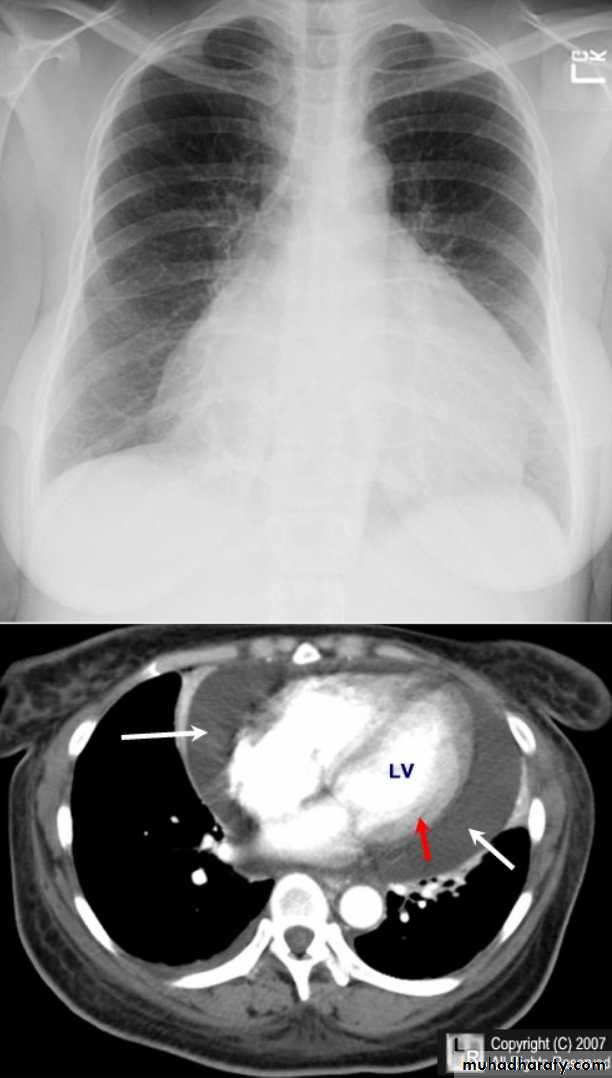

Pericardial effusions occur when fluid collects in the pericardial space (a normal pericardial sac contains approximately 30-50 mL of fluid).

Radiographic features

Plain radiographa very small pericardial effusion can be occult on plain film

there can be globular enlargement of the cardiac shadow giving a water bottle configuration known as Globe shape heart or pumpkin shape heart .

Pericardial effusion